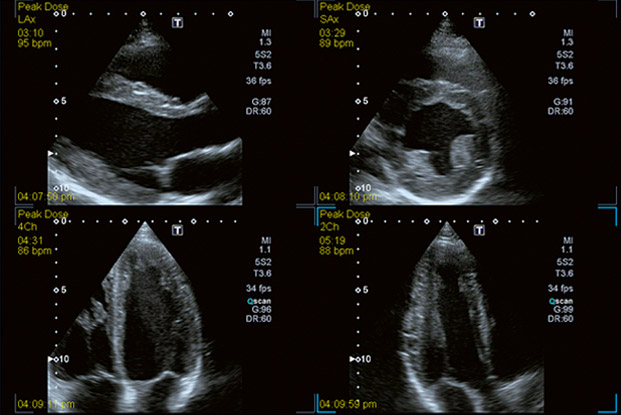

Canon Medical Systems' comprehensive Stress Echo package.

Stress Echo

Enables rapid view acquisition, rapid selection and easy regional wall motion scoring of both standard and user defined protocols for physiological and pharmacological stress echoes.